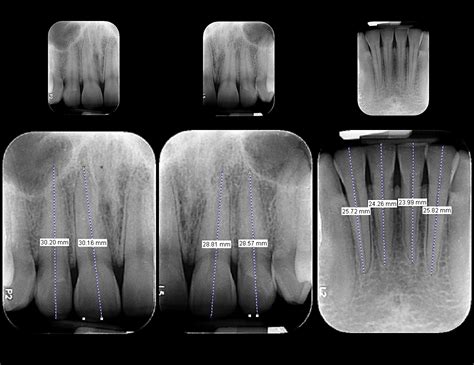

- Radiografía periapical: Cuando existen sospechas de que el origen del problema de salud bucodental se encuentra debajo de la línea de las encías o en la mandíbula, se emplea la radiografía periapical.

- Radiografía lateral del cráneo o telerradiografía: Es una radiografía lateral que abarca la totalidad del cráneo. Se emplea sobre todo para valorar aspectos como el desarrollo de las mandíbulas, los problemas de posición y la relación intermaxilar. Son un tipo de radiografía panorámica muy empleado en los tratamientos con ortodoncias.